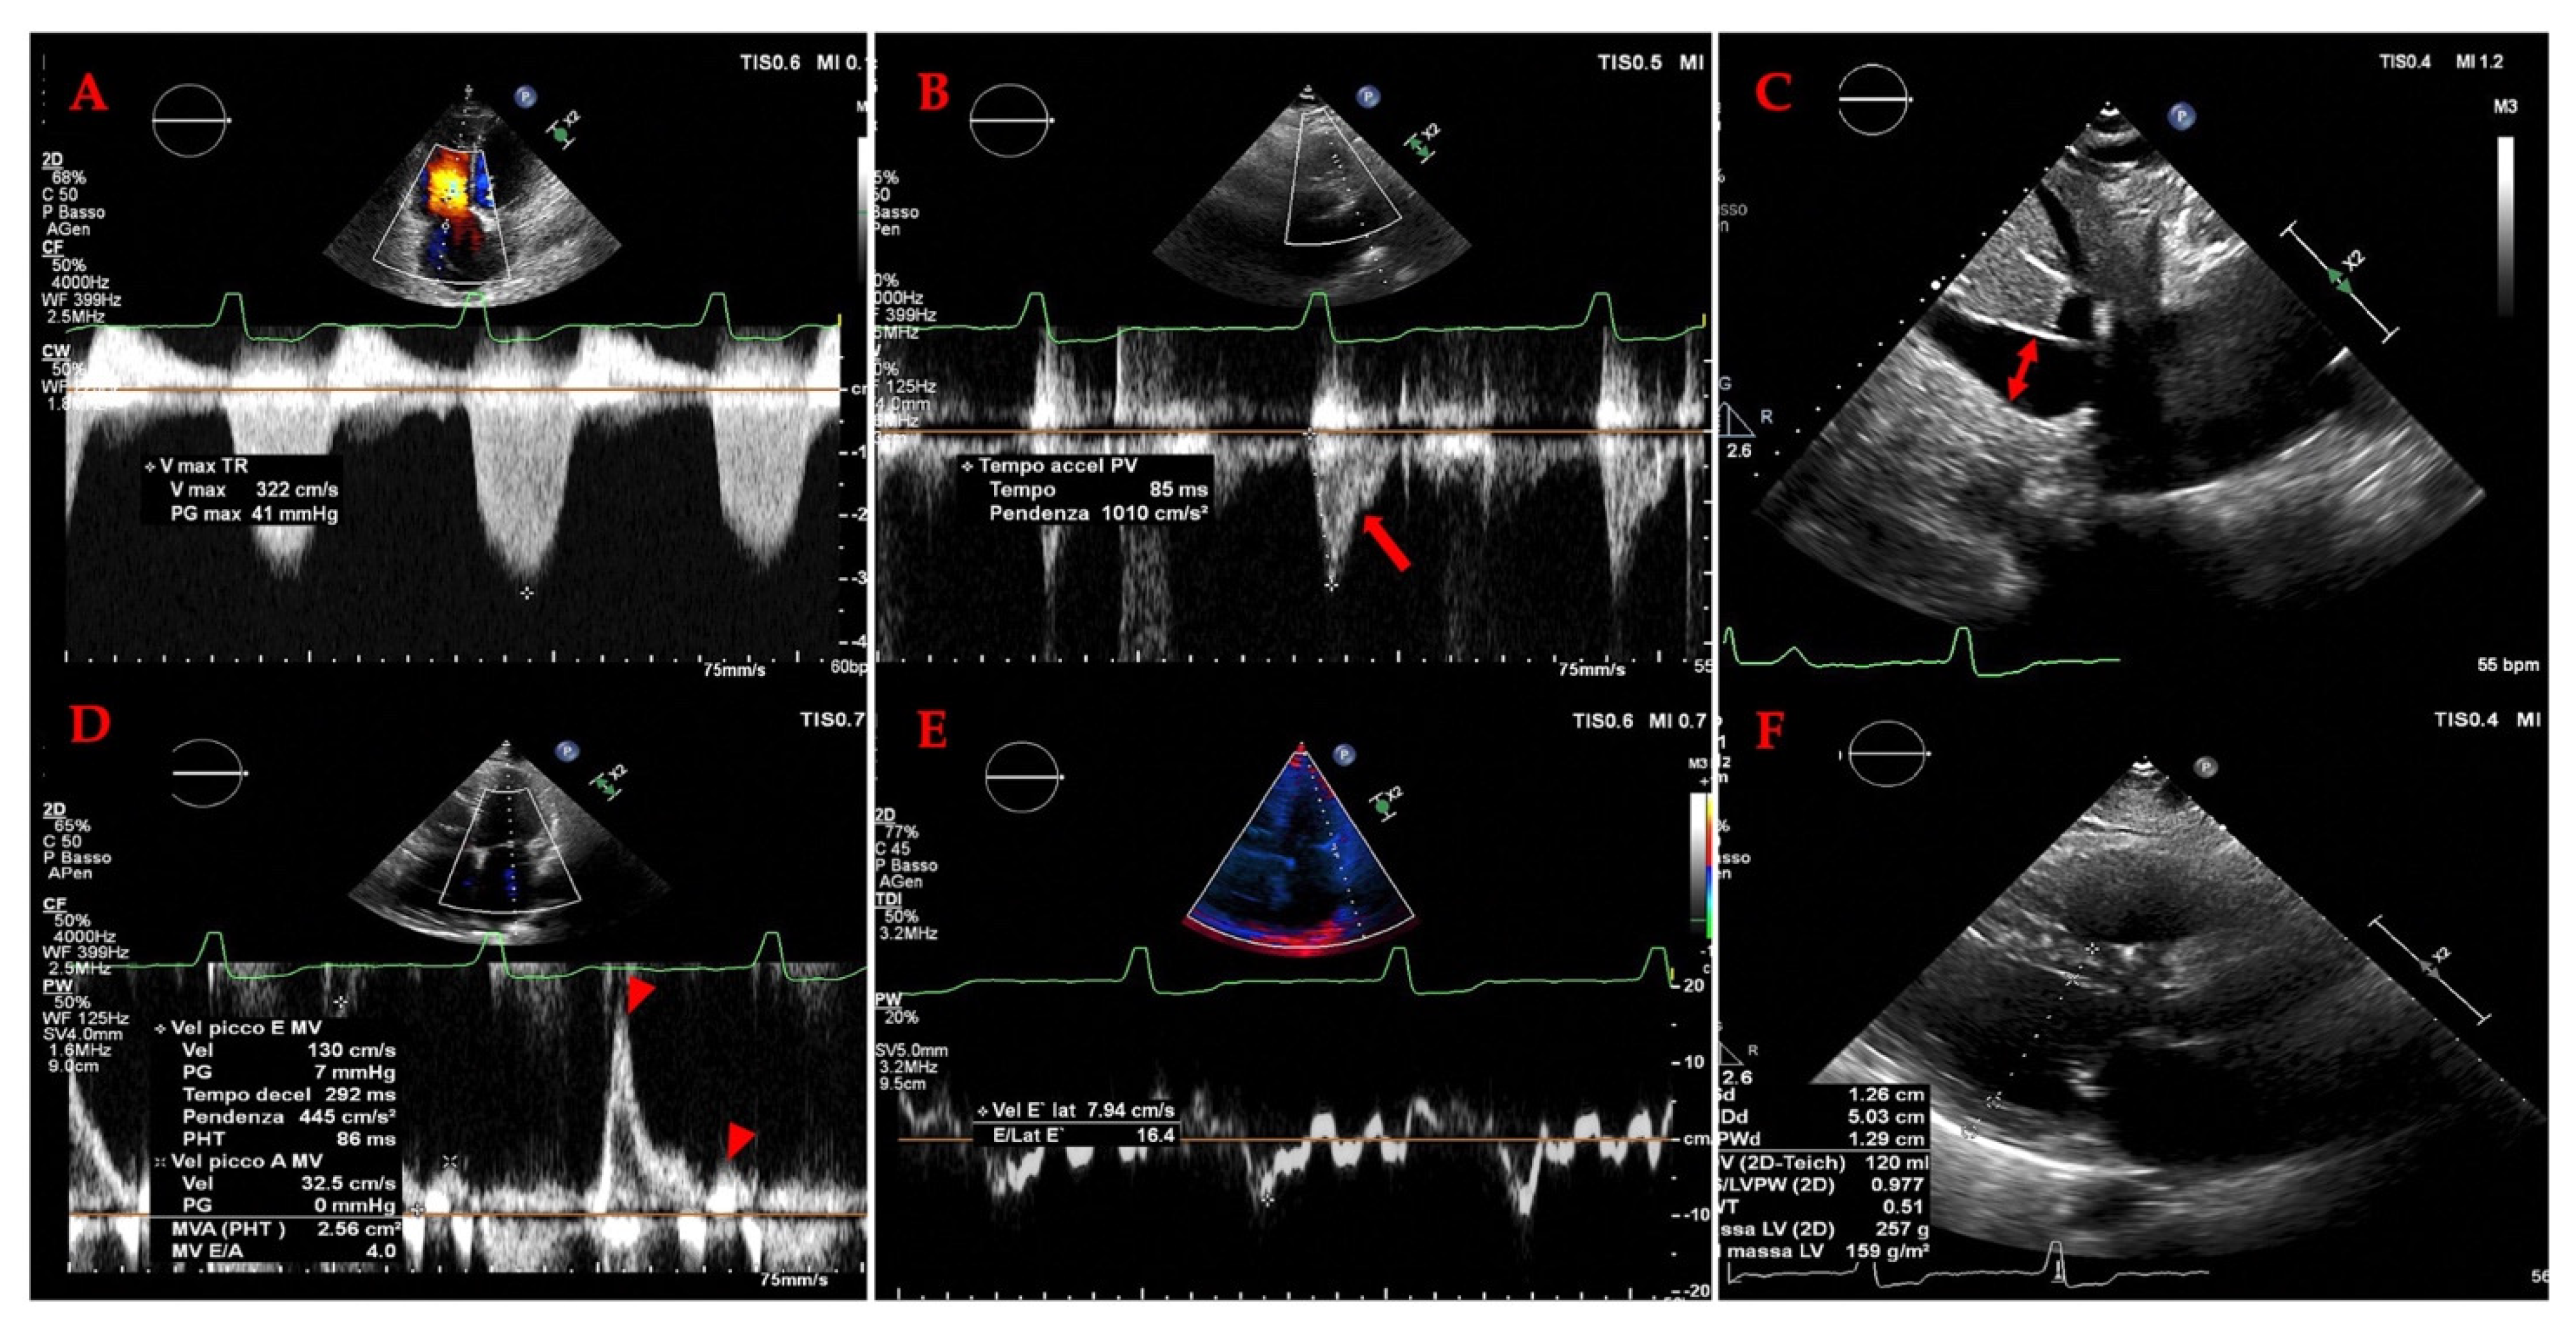

- Grading Venous Congestion: Venous congestion is categorized into grades 0–3 based on waveform alterations, a system known as VExUS (Venous Excess Ultrasound Score) (Figure 14) [63]. This grading system provides a practical method for assessing the severity of venous congestion in clinical settings (Figure 15).

- Hepatic Vein Doppler: In normal conditions, hepatic vein (HV) flow is pulsatile, corresponding to the RAP waveform. Pathologies like right ventricular dysfunction or tricuspid regurgitation can alter HV waveforms, and increasing RAP can reduce venous return during systole, leading to distinct changes in the waveform.

- Portal Vein Doppler: Normal portal vein flow is continuous, but severe venous congestion can cause pulsatility in the portal circulation. The pulsatility fraction (PVPF: [(Vmax − Vmin)/Vmax] × 100) quantifies this, with values above 30% indicating mild abnormalities and above 50% suggesting severe congestion [57]. Elevated PVPF is a strong predictor of acute kidney injury in post-cardiac surgery patients.

- Intra-Renal Vein Doppler: Similar to the portal vein, intra-renal veins show continuous flow under normal conditions, but congestion leads to a pulsatile pattern. This can manifest as a biphasic pattern in moderate congestion and a monophasic pattern in severe cases [114]. Altered intra-renal flow is associated with poor outcomes in heart failure and pulmonary hypertension patients [56,114].